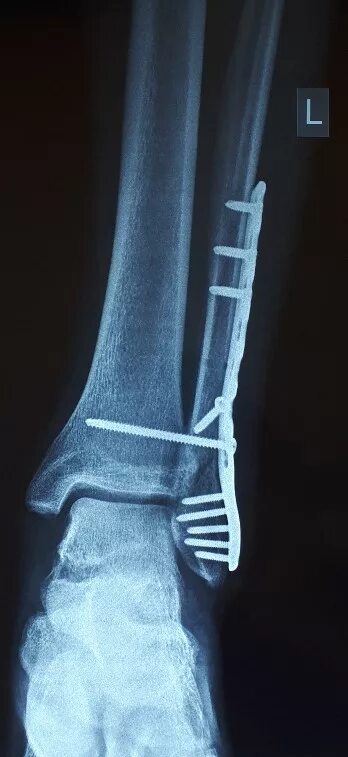

После остеосинтеза лодыжек